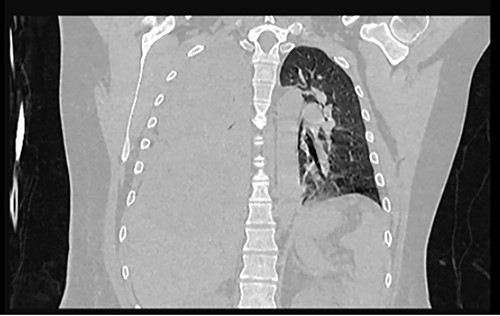

Examination revealed tachycardia, tachypnea, jaundice, dehydration, jugular vein distension, right lung hypoventilation, ascites, upper abdominal tenderness and bilateral lower limb edema. Laboratory workup highlighted neutrophilic leukocytosis, with WBCs exceeding 20 000/μl, along with an abnormal hepatic function panel. The latter showed hypertransaminasemia with ALT predominance over AST (344.7 U/L and 288.5 U/L, respectively), hyperbilirubinemia (10.01 μmol/L) and elevated values of ALP (909.1 U/L) and DHL (709.9 U/L). Of relevance, creatinine elevation (2.11 mg/dl), thrombocytosis (629 × 109/L) and positive D-Dimer (5780 ng/ml) were also noted, so acute kidney injury management and thromboprophylactic measures were initiated. A chest X-ray (CXR) showed a massive right pleural effusion (Fig. 1) and an abdominal ultrasound (US) revealed hepatomegaly with a right nodule (Fig. 2). After further evaluation, tomographic evidence of a right pleural effusion occupying 100% of the lung (Fig. 3) and a 20 cm hypodense, nodular lesion in the right liver (Fig. 4) were identified. These findings were suggestive of an ALA concomitant with an empyema. The patient was admitted into the intensive care unit and prepared for surgery.

Frontal chest CT at admission: right pleural effusion occupying 100% of the lung.